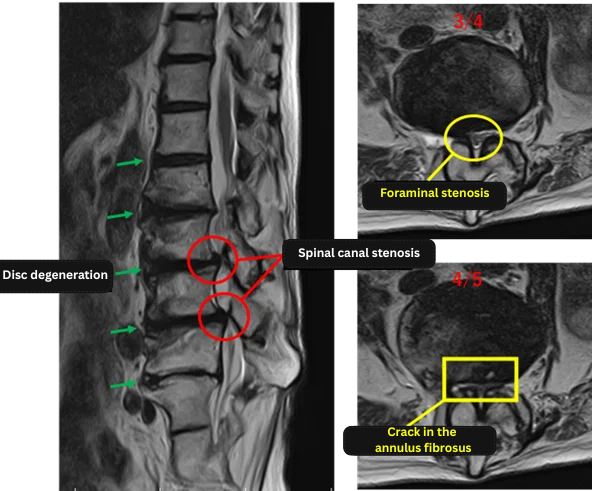

Imaging and findings

L1/2: Intervertebral disc degeneration

L2/3: Disc degeneration with reduced disc height

L3/4: Disc degeneration, reduced height, disc bulging, lumbar spinal canal stenosis

L4/5: Disc degeneration, bulging, reduced height, lumbar spinal canal stenosis, annular tear

L5/S1: Disc degeneration, reduced height, disc bulging

The above findings were also observed on the imaging.

Based on these findings, L3/4 and L4/5 showed disc degeneration, spinal canal stenosis, and annular tears, and were considered highly likely to be the primary sources of the patient’s symptoms.